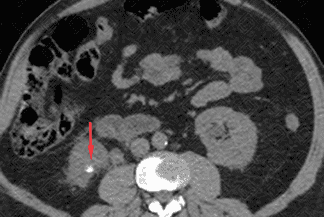

Texto alternativo para a imagem Figuras 1 e 2. Créditos: Dra Elazir Mota - Rio de Janeiro/RJ

Descrição das figuras 1 e 2: Tomografia computadorizada do abdome sem a administração do contraste venoso evidencia cálculo no terço inferior do rim direito (seta vermelha), medindo 0,6 cm e com densidade de 780 UH (figura 1).

• Tomografia computadorizada do abdome: Exame padrão-ouro. Na tomografia computadorizada do abdome é sempre importante descrever a quantidade de cálculos, suas dimensões, densidade (por meio da densidade, podemos saber a respeito da composição do cálculo) e localização. Importante lembrar também que para avaliação de litíase, seja ela renal, ureteral ou vesical, o estudo deve ser feito sem a administração do contraste venoso. A administração de contraste fica reservada para avaliação de complicações, como suspeita de pielonefrite ou abcessos renais. Vale destacar que o cálculo de Indinavir (inibidor de protease - medicação para HIV) também não é visualizado na tomografia.